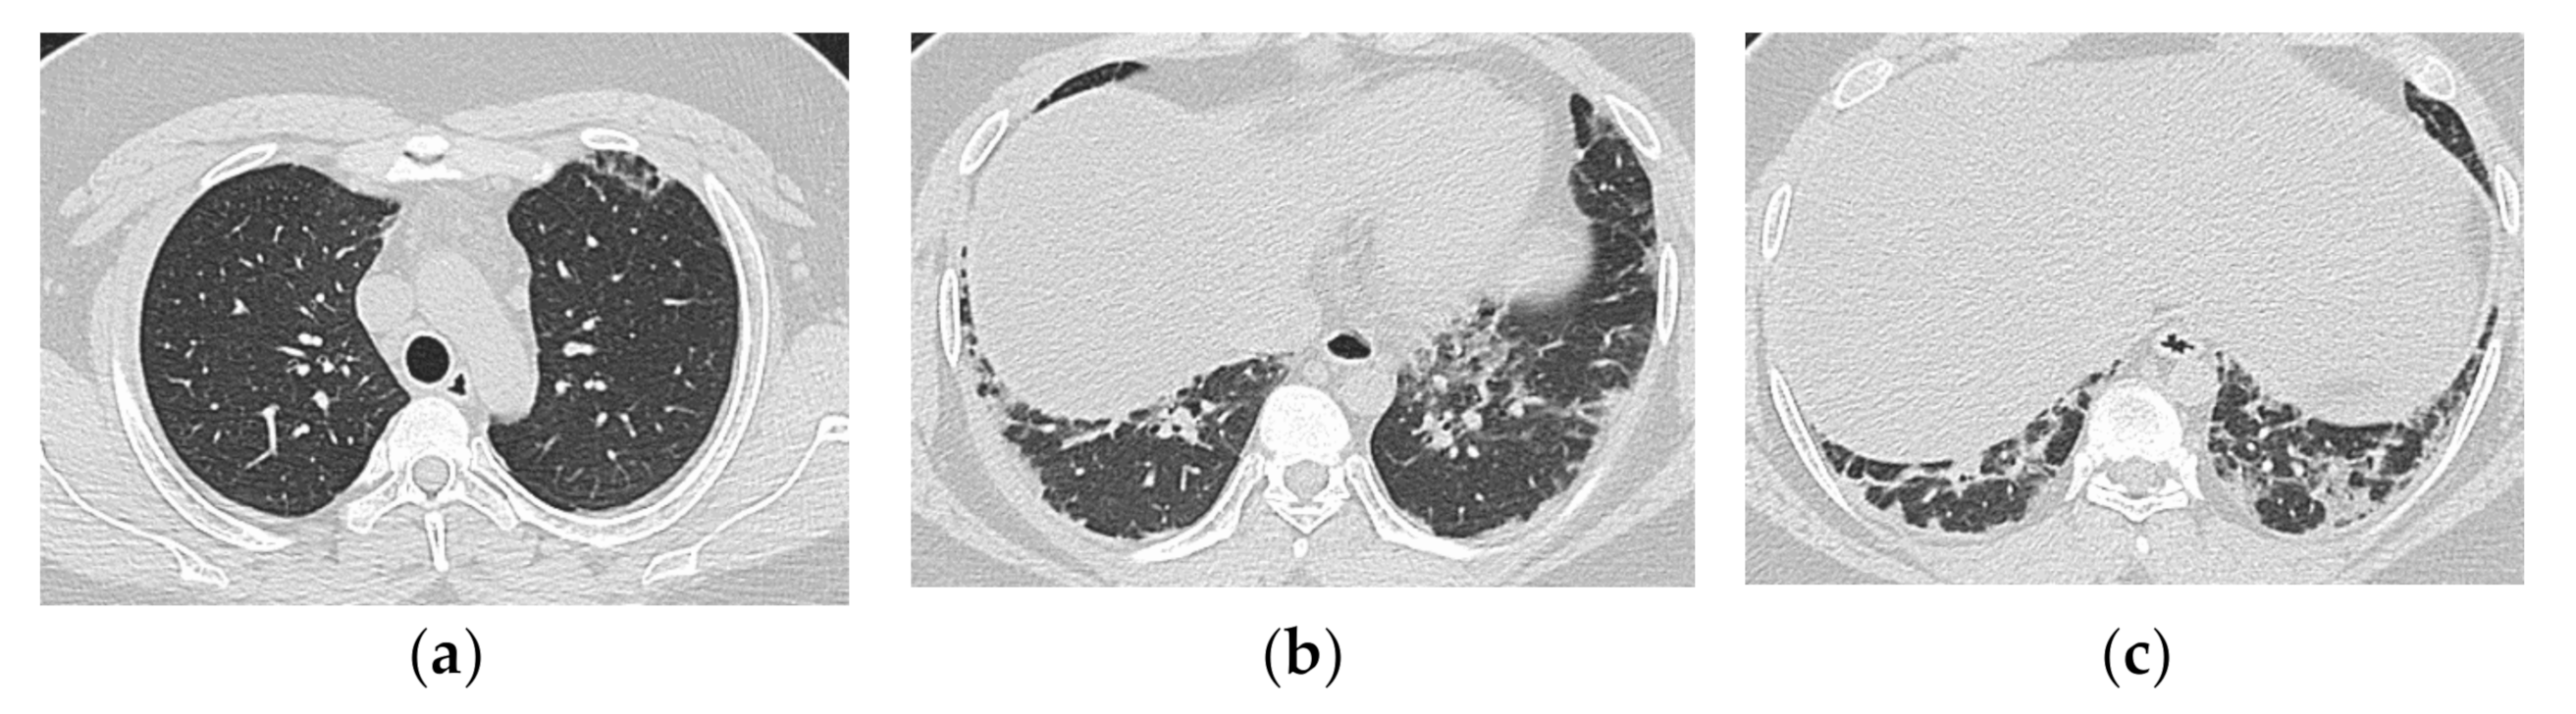

4. HRCT Findings in Relation to the Poorer Prognosis